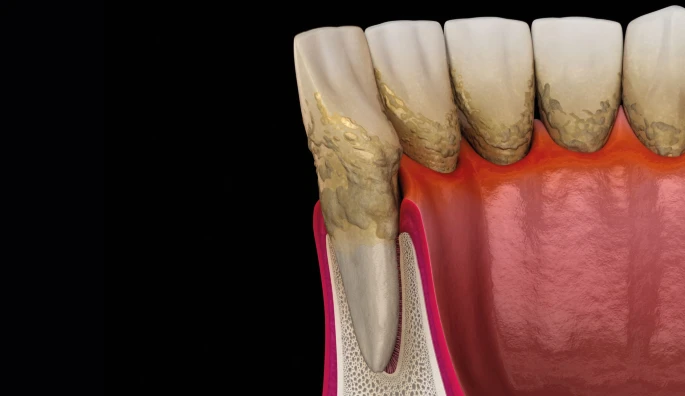

✓ Limpeza profissional resolve

✓ Limpeza profissional resolve

O que é: Tártaro (cálculo dental) é a placa bacteriana que endureceu. Não sai com escova nem com fio dental — só com ultrassom ou instrumentos profissionais. Quanto mais acumula, mais irrita e inflama a gengiva.

O que fazer: Limpeza periodontal profissional (raspagem com ultrassom) e orientação de higiene para evitar o acúmulo. Em casos de tártaro subgengival (abaixo da gengiva), é necessária raspagem subgengival com anestesia.

Tudo sobre a periodontite

← arraste para ver os 4 estágios →

A forma avançada da doença: a inflamação passou da gengiva e chegou ao osso que segura o dente. O osso já perdido não volta — mas o avanço pode ser parado. E ela age em silêncio, sem dor. Toque em cada tópico:

O que é periodontite

A periodontite — a antiga "piorréia" — é o estágio avançado. A inflamação ultrapassou a gengiva e atingiu o ligamento e o osso. A bolsa aprofunda, bactérias proliferam embaixo da gengiva e o osso vai sendo destruído: lento, silencioso e irreversível. O tratamento controla a doença e impede o avanço — mas o osso já perdido raramente volta sem cirurgia. Por isso o diagnóstico precoce é tudo.

A bactéria por trás

Não é uma bactéria "do mal" genérica — é uma disbiose: o desequilíbrio entre as mais de 700 espécies que vivem na boca. Nas bolsas predominam bactérias anaeróbias agressivas, o chamado "complexo vermelho": Porphyromonas gingivalis, Treponema denticola e Tannerella forsythia. Elas soltam enzimas que destroem o colágeno e driblam a defesa do corpo.

Não é uma bactéria "do mal" genérica — é uma disbiose: o desequilíbrio entre as mais de 700 espécies que vivem na boca. Nas bolsas predominam bactérias anaeróbias agressivas, o chamado "complexo vermelho": Porphyromonas gingivalis, Treponema denticola e Tannerella forsythia. Elas soltam enzimas que destroem o colágeno e driblam a defesa do corpo.Como é o tratamento

O dentista faz a parte dele: raspagem e alisamento radicular — limpa o tártaro embaixo da gengiva e alisa a raiz — mais o controle da infecção. Mas 90% é com você: sem mudar a escovação em casa, tudo volta.